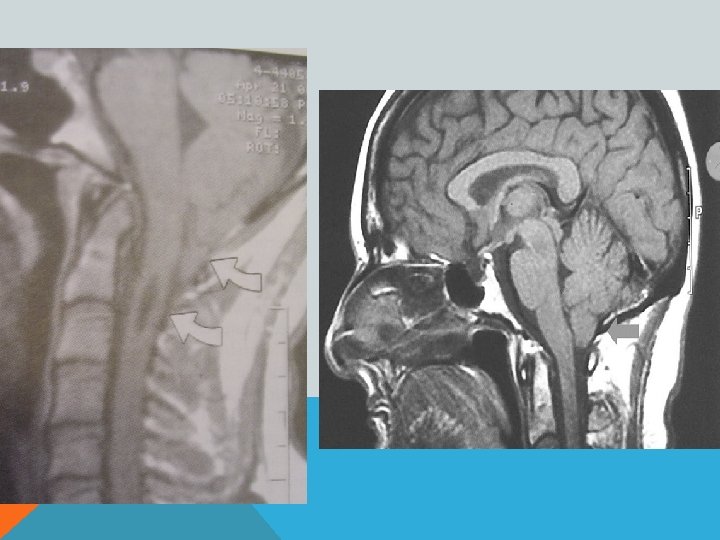

ПОРОК АРНОЛЬДА-КИАРИ 1 Увеличение миндалин мозжечка, их опущение в большое затылочное отверстие и далее, в спинномозговой канал- «нижний» вариант. Характерно образование сирингомиелической полости в шейном отделе спинного мозга. Основные клинические проявления- сирингомиелия.

ПОРОК АРНОЛЬДА-КИАРИ 1 Увеличение горки червя мозжечка и его смещение в межножковую цистерну- «верхний» вариант. Основные клинические проявления- расстройство равновесия (головокружение? )

ПОРОК АРНОЛЬДА-КИАРИ 2 Увеличение миндалин мозжечка, их опущение в большое затылочное отверстие и далее, в спинномозговой канал. «Щелевидный» 4 -й желудочек. Гипоплазия подушки моста мозга. Гипо-/аплазия мозолистого тела. Сирингомиелическая полость в шейном отделе спинного мозга. Фенестрация фалькса (серпа мозга) и т. д. В 70% сочетается со спинномозговой грыжей.